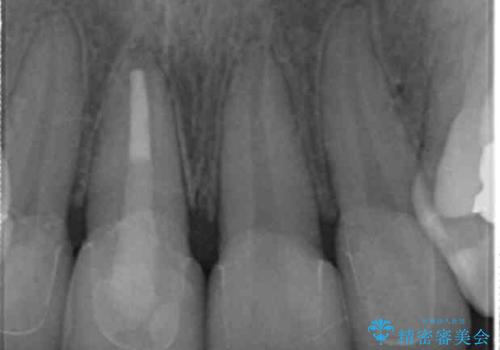

右上1番は、根の治療のやり直しをしています。

- 63.8万円(右上4~左上2:emaxクラウン 7万円x6本、仮歯 1万円x6本、歯周外科手術 15万円、右上1:精密根管再治療 9万円およびファイバーコア2万円)費用は治療当時の料金となります

保険治療の前歯の被せものの縁(マージン)が歯茎の中まで及んでいたため、歯周外科手術を行い、マージンが歯肉縁下深くならないように設定しました。